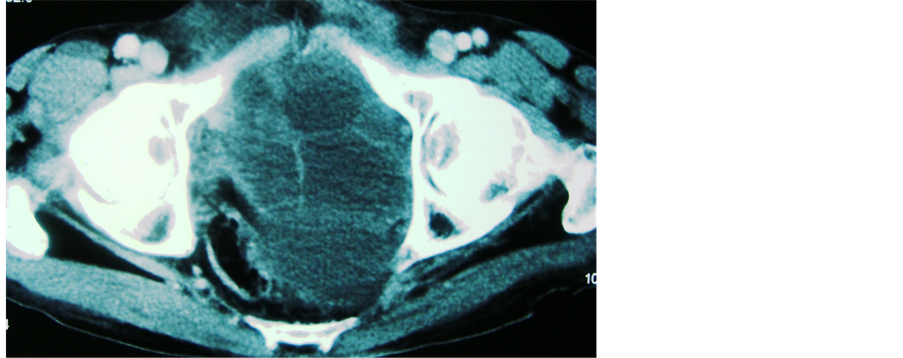

A 50 year male presented with retention of urine for the last one day. He gave past history of difficulty in micturition for last five years along with pain in right loin for last six months. Examination revealed a firm, smooth, non mobile and non tender mass in suprapubic region along with a ballotable mass in right lumbar region. On per rectal examination, a smooth cystic mass was felt anteriorly in the rectovesical pouch. Serum creatinine, urea and electrolytes, liver function test and urine analysis were normal. Ultrasound examination revealed a cystic mass in pelvis suggestive of a hydatid cyst with bilateral hydronephrosis. There was no lesion in the liver. Computerized tomography (CT) scan revealed a pelvic hydatid cyst with bilateral hydronephrosis with non functioning right kidney (Figure 1, Figure 2). Indirect haemagglutination test for hydatid disease was negative.

Figure 1. CECT of 1st case showing pelvic hydatid cyst.